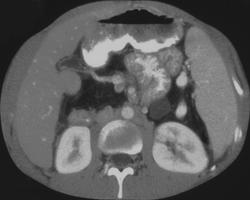

CASE NUMBER 8

Pancreatic Cancer